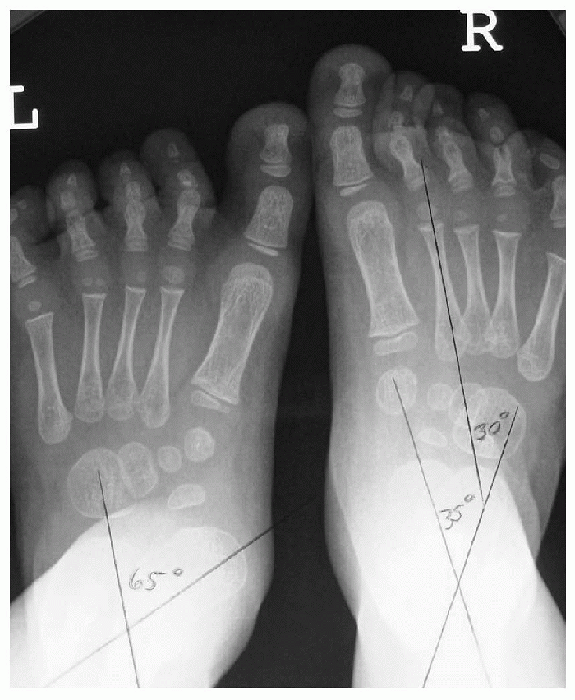

(AP), lateral, oblique, and calcaneal axial (Harris-Beath view), in a

angle (Fig 4.5-4) formed by the bisection of

the calcaneus and talus. As the calcaneus everts and the talus

plantarflexes and adducts with pronation, this angle increases. Normal

pediatric values range from 35 to 50 degrees at birth to 5 years of age

and decrease to 15 to 35 degrees in children more than 5 years of age.

Normal adult values are around 18 degrees. The relationship between the

![]() |

Figure 4.5-4 Sixty-five-degree talocalcaneal angle on left foot. This angle increases with pronation.